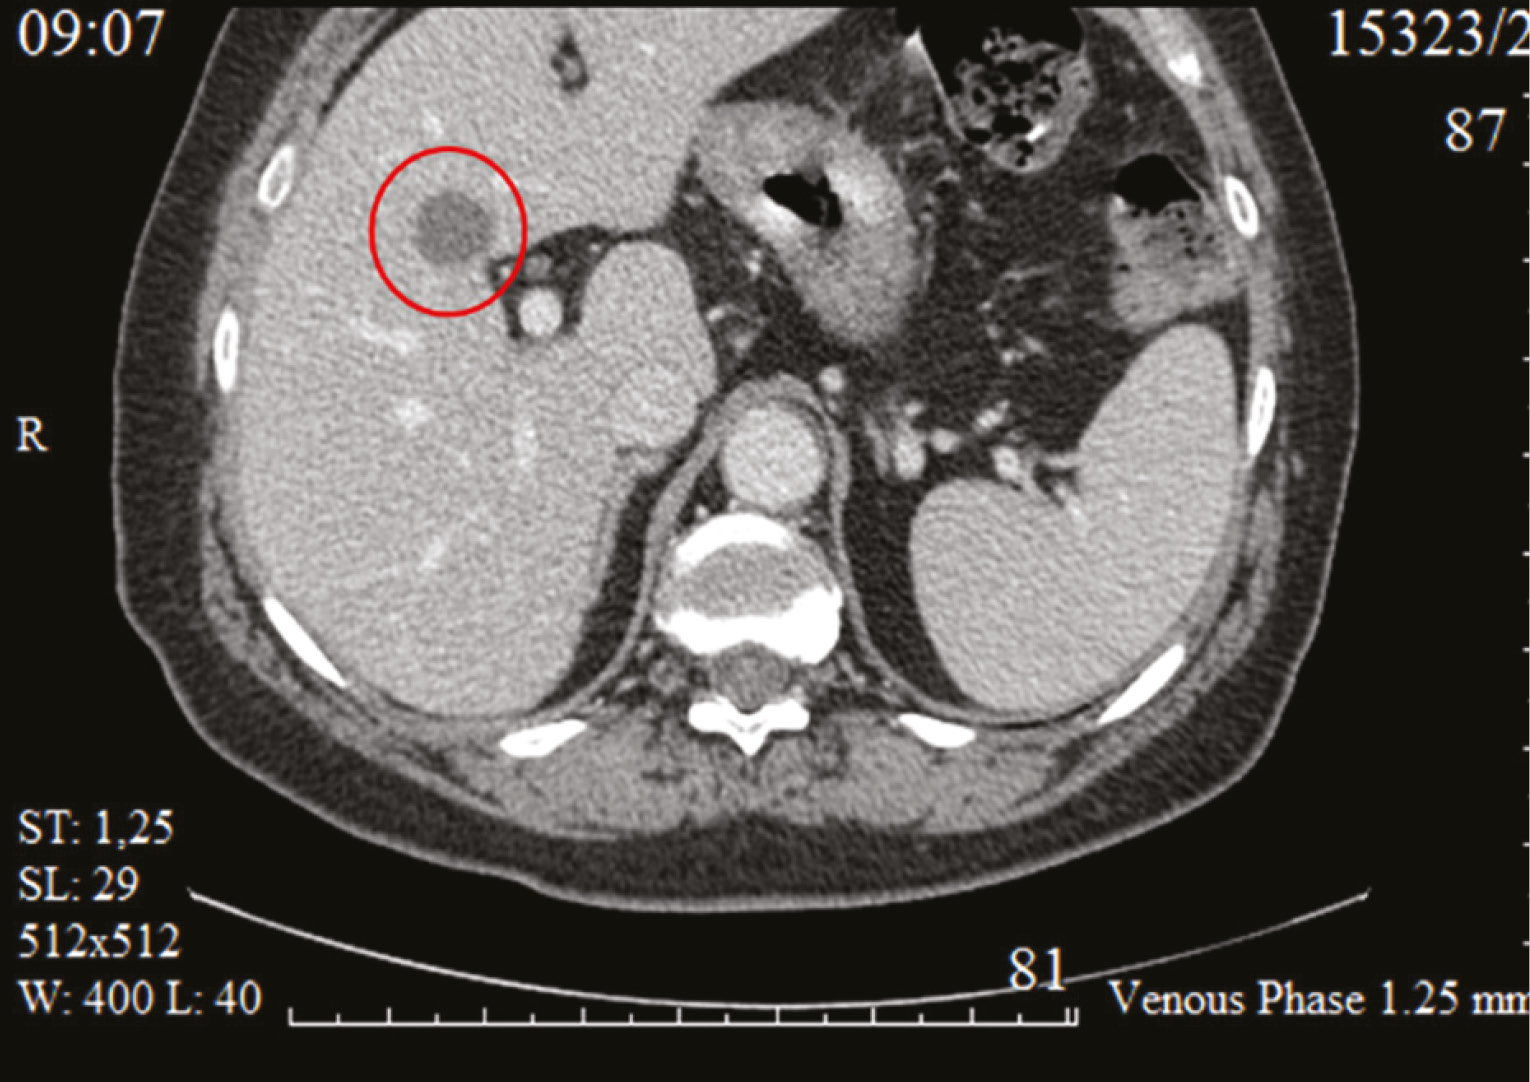

Abdominal magnetic resonance imaging (MRI) dated December 2022 (reviewed at the N.N. Blokhin National Medical Research Center of Oncology): hepatic parenchyma shows signs of cirrhosis. In segments S8/S5, a HCC nodule measuring 2.9 × 2.4 cm was identified. No tumor lesions were detected in other parts of the liver. The portal vein was dilated to 19 mm (normal values: ≤14 mm), without signs of thrombosis. Esophageal varices were present. The spleen was enlarged to 18 cm in length (normal values: 12–14 cm). The splenic vein measured up to 1 cm in diameter (normal values: ≤1.5 cm; Fig. 1).

Fig. 1. MRI of the abdominal cavity from 01.2023. Liver parenchyma structure with signs of cirrhosis. In S8/S5, a tumor node of HCC measuring 2.9×2.4 cm is determined. In other parts of the liver — without obvious tumor formations. The portal vein is dilated to 1.9 cm, without signs of thrombosis. Varicose veins of the esophagus. The spleen is enlarged to 18 cm.